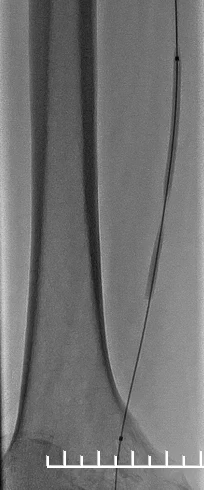

1.造影评估:左股动脉翻山入路,经鞘管造影见右股浅动脉中下段局限重度狭窄,远端股腘动脉、膝下动脉延迟显影,血流流速缓慢(图2,3,4)。

(图2)

(图3)

(图4)